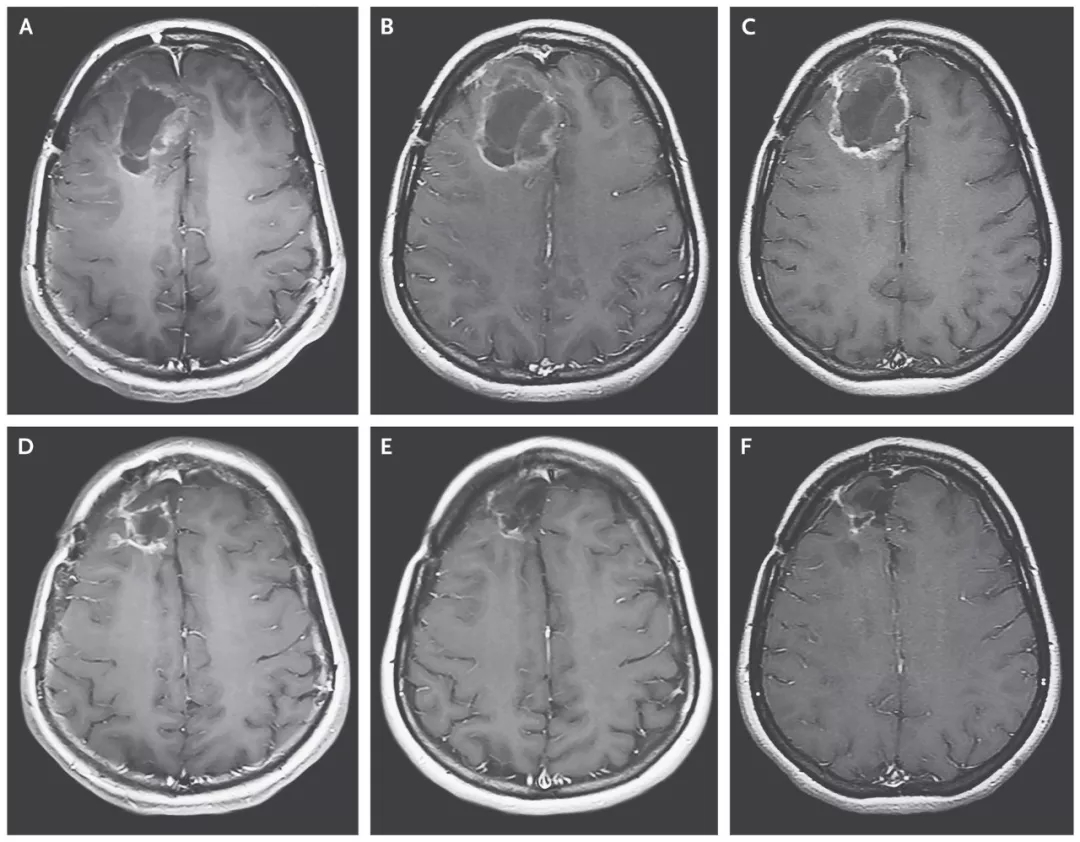

(患者脑部肿瘤的缩小清晰可见)

比“癌王”还凶险的脑癌 3年生存率翻5倍

结果显示:治疗组的中位生存期是12.5个月,与11.3个月的历史数据相差无几;治疗组的2年生存率为21%,已比历史数据(14%)高出50%;3年生存率同样为21%,而历史数据仅为4%。经过溶瘤病毒的治疗,生存率猛增5倍!

20岁多岁的斯蒂芬妮·利普斯科姆是一名脑胶质母细胞瘤复发患者,被医生断言仅剩几个月的生命。幸运的是,她成为了首名接受这项试验性病毒治疗的患者。在接受治疗后,她大脑里的肿瘤不断缩小。在2014年,肿瘤竟彻底消失了。这个“奇迹”经美国CBS电视台知名栏目《60分钟》报道后,震惊全美。